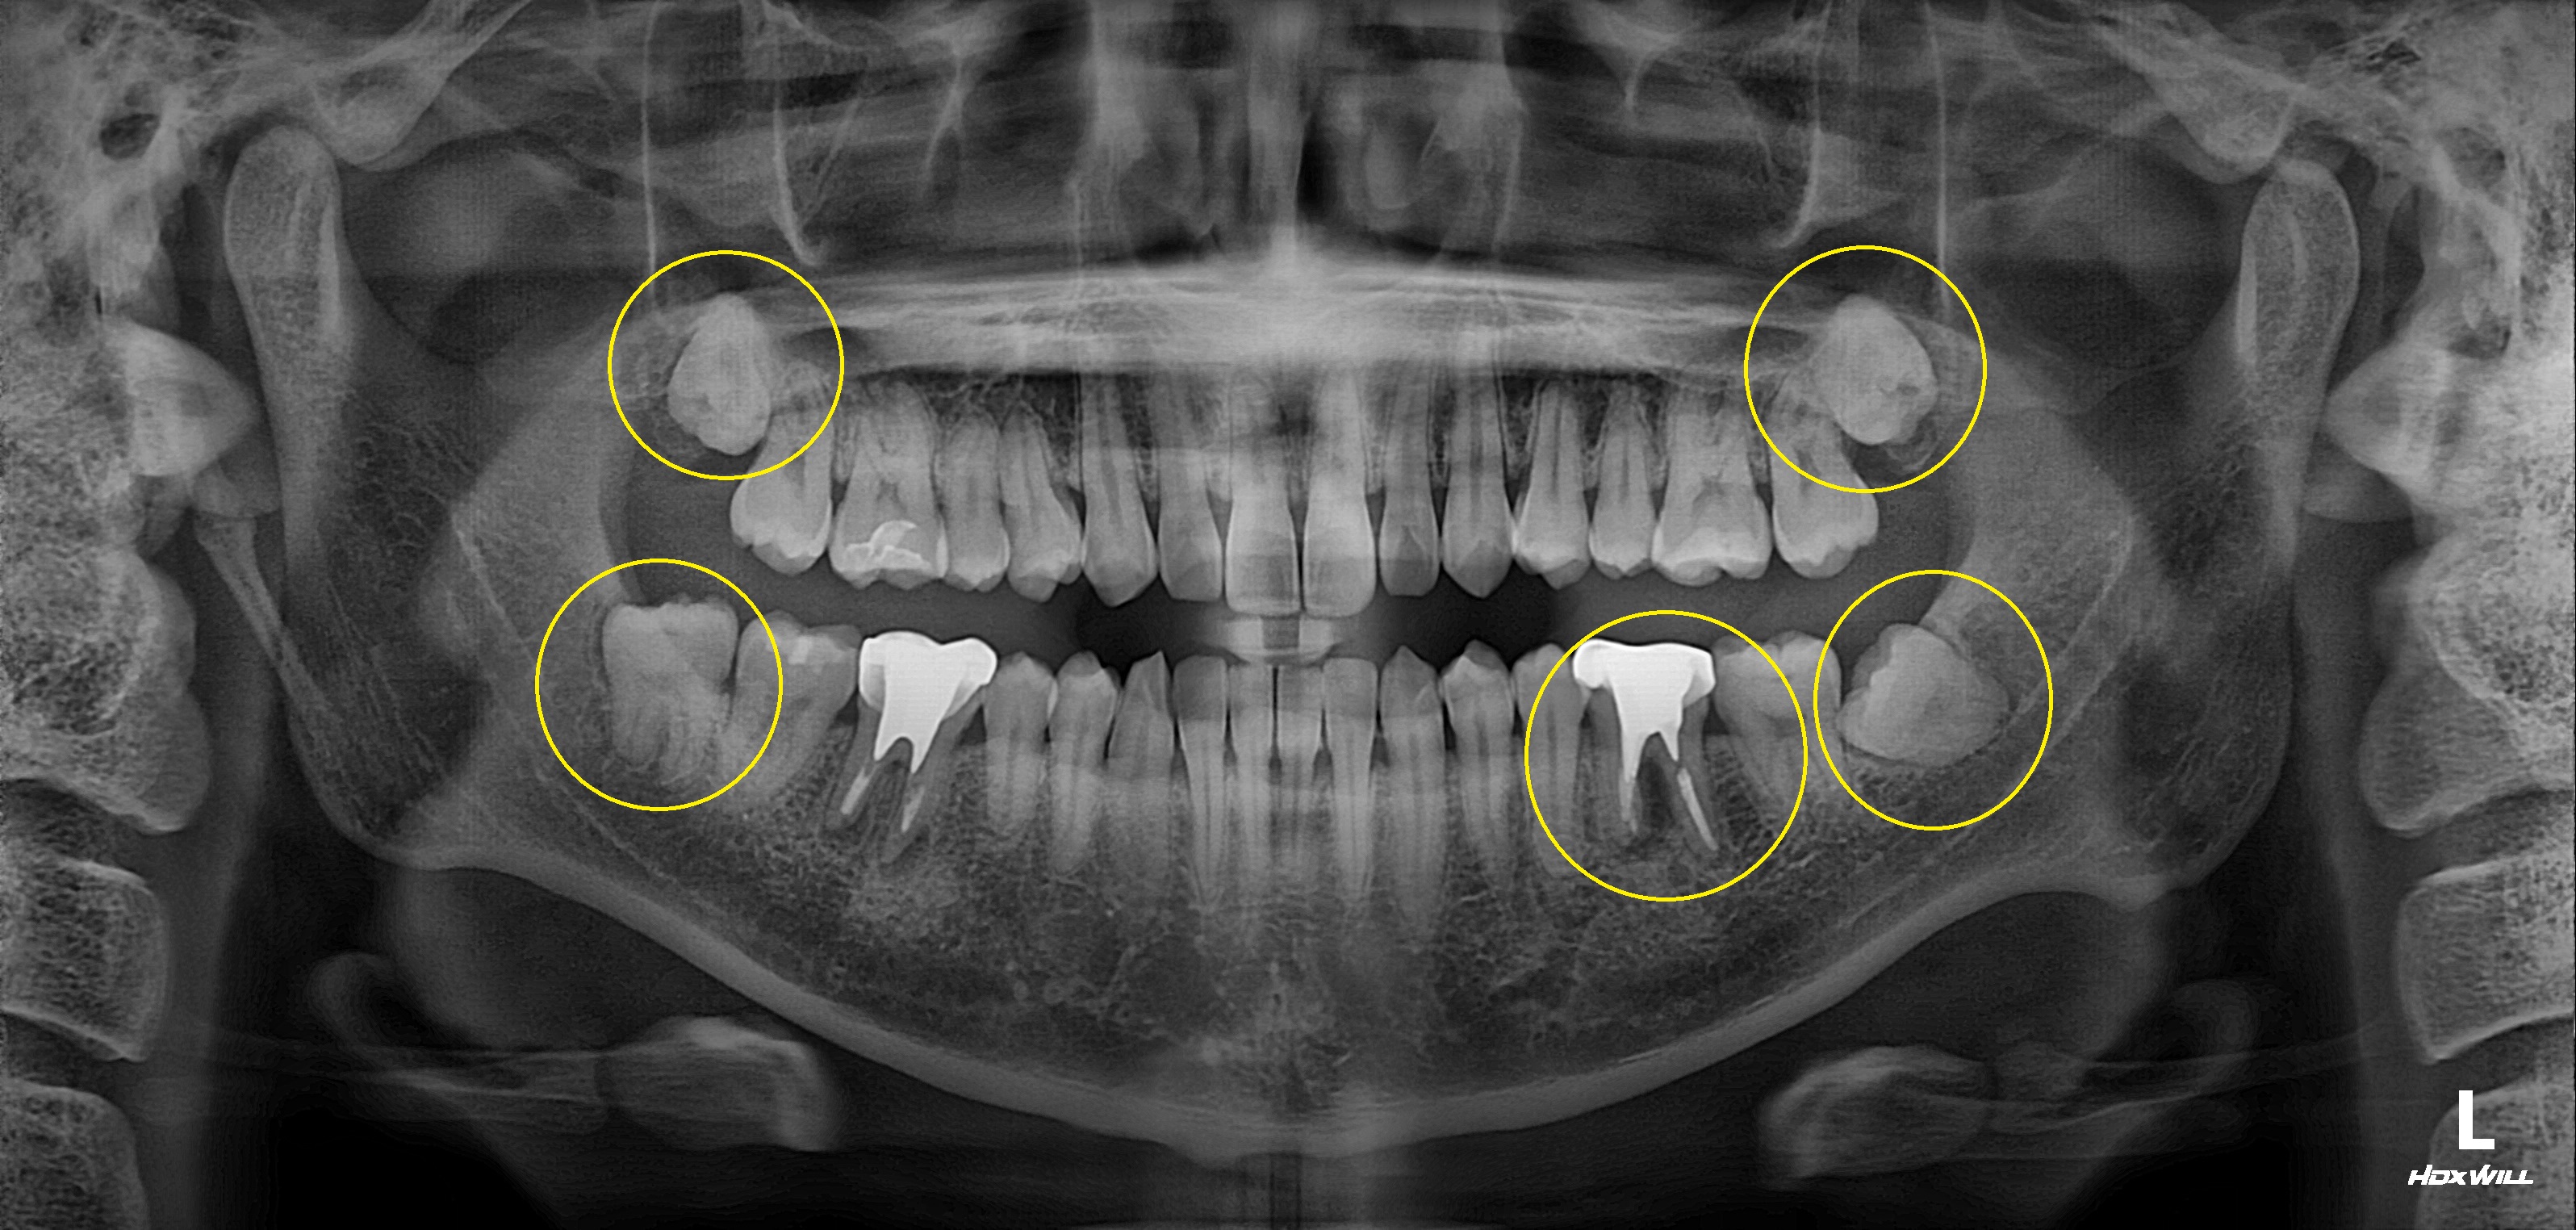

구치부 임플란트 식립사례

전후사진